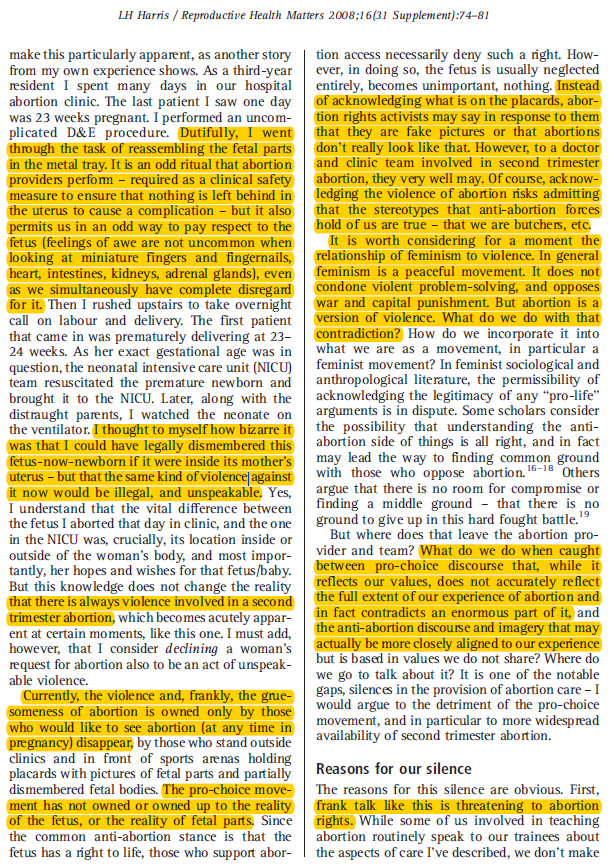

It's unsurprising that few will defend abortion as it is, preferring instead to veil it in euphemism--words meant to conceal, not reveal.

"Choice." https://bit.ly/3otI2X4

It's unsurprising that few will defend abortion as it is, preferring instead to veil it in euphemism--words meant to conceal, not reveal.

"Choice." https://bit.ly/3otI2X4